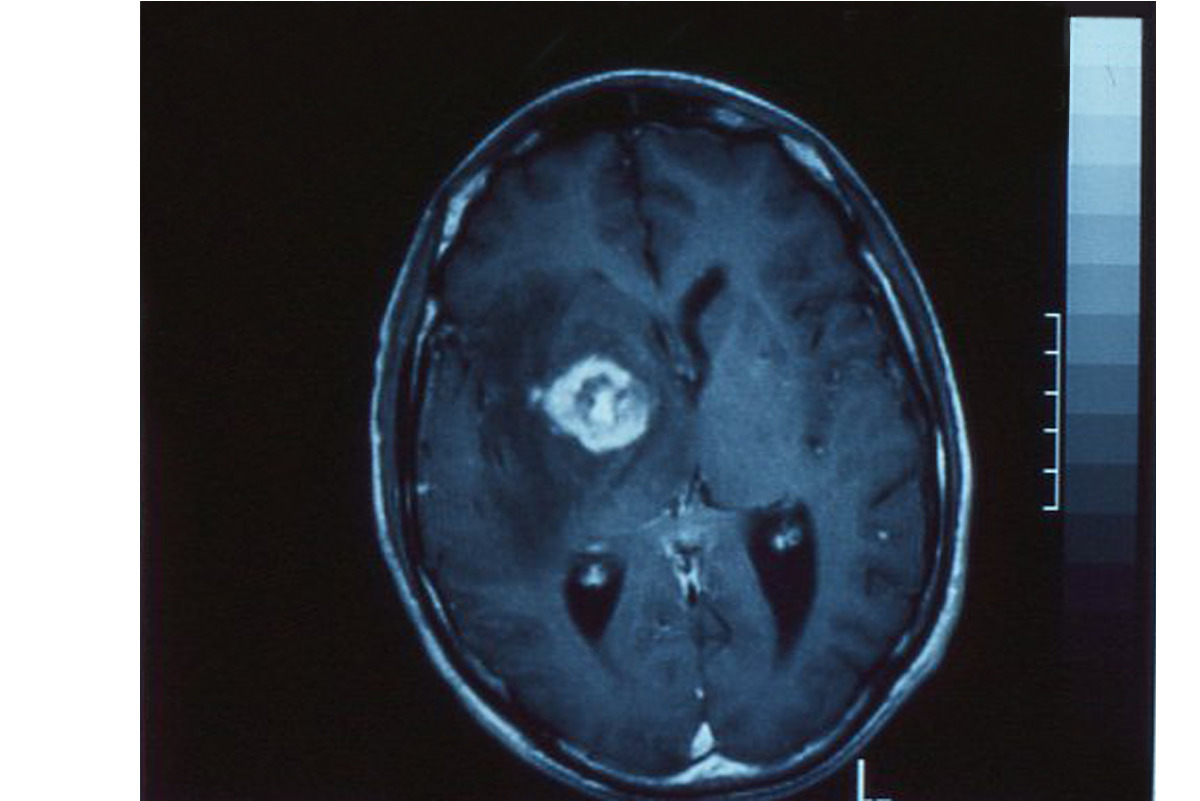

Il s’agit d’une toxoplasmose cérébrale chez un patient immunodéprimé (SIDA).

L’encéphalite toxoplasmique focalisée est la manifestation clinique la plus fréquente chez les malades immunodéprimés. Elle associe la fièvre à une symptomatologie neurologique très variée : céphalées, déficits moteurs ou sensitifs, comitialité, troubles psychiatriques. La tomodensitométrie ou l’imagerie par résonance magnétique (IRM) montrent habituellement un ou plusieurs abcès dont la périphérie prend fortement le produit de contraste. On peut également observer des encéphalites diffuses, sans image radiologique.